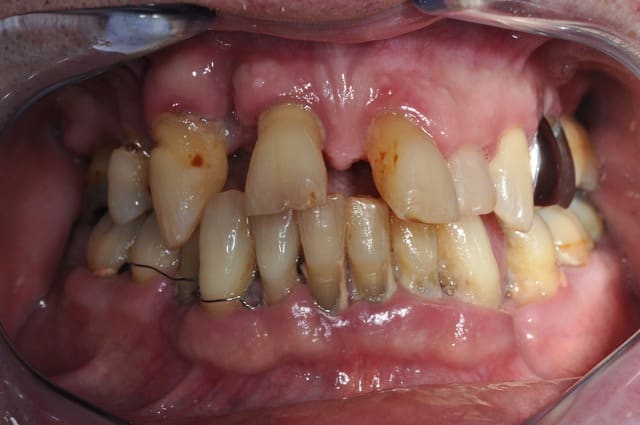

Patient perdu de vue pendant 1 an seulement après son ttt paro. Pffff.

Non, juste un paquet d'extractions des dents non conservables à l'époque, et un débridement radiculaire non chirurgical. La réévaluation était prévue à 2 mois avant d'éventuellement aller plus loin. En dépannage, et pour éviter l'adjointe, j'avais collé la couronne de la 11 aux voisines.

C'est sûr, ma "motivation" du patient est un échec total. Il me dit qu'il est "habitué, maintenant" à la situation. On verra s'il s'habitue aussi bien au complet bimax.